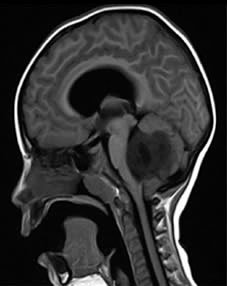

El tumor de la fosa posterior es una neoplasia que ocupa la fosa craneal posterior que se encuentra limitada por el clivus, en la zona inferior por el foramen mágnum, posterior por la concha del hueso occipital y a sus laterales por la porción petrosa mastoidea del hueso temporal y arte del hueso parietal (Fajardo,2001). Este tumor es el segundo tipo de cáncer infantil más común; representa en la población pediátrica el 48% del total de esta y su incidencia es de 4,5 por cada 100.000 niños. Afecta en mayor parte al género masculino con 57% del grupo poblacional reportado. Dosterceraspartes aproximadamente, de todos los tumores intracraneales que aparecen en niños entre 2 y 12 años de edad, son los infratentoriales pertenecientes a la zona posterior del cerebro (Cano, 2010).